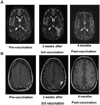

Purpose: To assess the feasibility, safety, and toxicity of autologous tumor lysate-pulsed dendritic cell (DC) vaccination and toll-like receptor (TLR) agonists in patients with newly diagnosed and recurrent glioblastoma. Clinical and immune responses were monitored and correlated with tumor gene expression profiles.

Experimental design: Twenty-three patients with glioblastoma (WHO grade IV) were enrolled in this dose-escalation study and received three biweekly injections of glioma lysate-pulsed DCs followed by booster vaccinations with either imiquimod or poly-ICLC adjuvant every 3 months until tumor progression. Gene expression profiling, immunohistochemistry, FACS, and cytokine bead arrays were performed on patient tumors and peripheral blood mononuclear cells.

Results: DC vaccinations are safe and not associated with any dose-limiting toxicity. The median overall survival from the time of initial surgical diagnosis of glioblastoma was 31.4 months, with a 1-, 2-, and 3-year survival rate of 91%, 55%, and 47%, respectively. Patients whose tumors had mesenchymal gene expression signatures exhibited increased survival following DC vaccination compared with historic controls of the same genetic subtype. Tumor samples with a mesenchymal gene expression signature had a higher number of CD3(+) and CD8(+) tumor-infiltrating lymphocytes compared with glioblastomas of other gene expression signatures (P = 0.006).

Conclusion: Autologous tumor lysate-pulsed DC vaccination in conjunction with TLR agonists is safe as adjuvant therapy in newly diagnosed and recurrent glioblastoma patients. Our results suggest that the mesenchymal gene expression profile may identify an immunogenic subgroup of glioblastoma that may be more responsive to immune-based therapies.